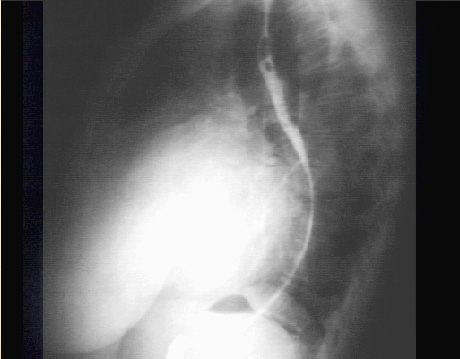

The lateral view, with barium swallow, demonstrates marked posterior displacement of the esophagus by the giant left atrium.